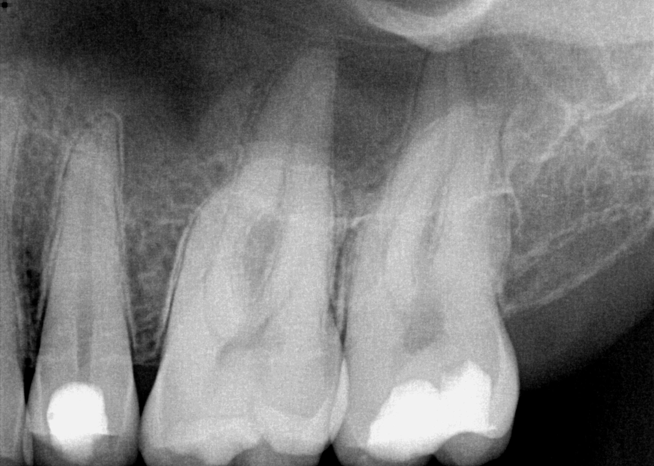

A patient presented with acute pain and facial swelling. Tooth No. 6 was positive to percussion, without sensitivity to air, sweets, or temperature stimulus. Treatment options were discussed with the patient. The decision was to complete endodontic therapy to eliminate the pain (Figure 1). Definitive long-term final-restoration treatment options were presented using a fiber post and core with full-coverage CAD/CAM crown.

Fig 1. A preoperative radiograph was taken, the patient was administered local anesthetic, and a digital estimated measurement was recorded for initial working length.

Figure 1